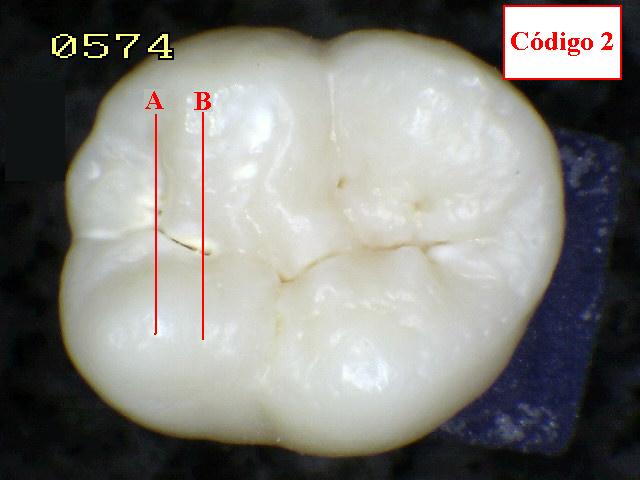

| CÓDIGO 2: Evidente cambio visual del esmalte

en estado húmedo y permanece después de secar. |

| Al observar el diente verá

una decoloración mancha

blanca o marrón en el fondo de la fosa y fisura y

que desborda hacia las paredes (más ancha que la fosa y fisura)

las manchas no tienen brillo y es consistente con desmineralización. |

Espécimen 5 |

Espécimen Nº 28 |

|

| Corte sagital A:

Observe como el corte en la fosa presenta caries en dentina,

compatible con un código 2 histológico |

Corte sagital B: En la fisura es un

código 2 histológico |